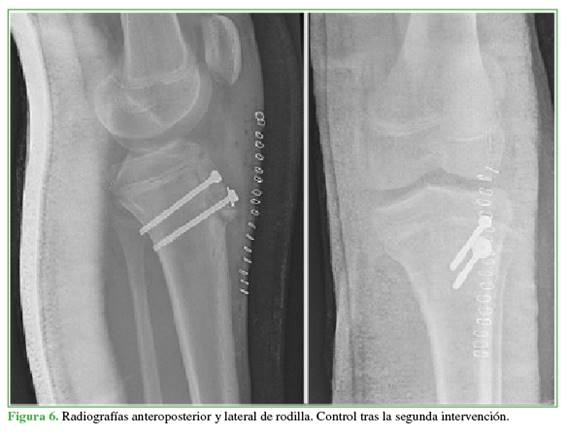

Mediante un abordaje anterior, se extrajo el material de osteosíntesis y se realizó una osteosutura del fragmento óseo de la TTA con una sutura trenzada de poliéster no absorbible (Orthocord®, Johnson & Johnson, Madrid, España). Se crearon dos túneles perpendiculares en la tibia por los que se pasaron las suturas. A continuación, se redujo la fractura y se fijó con dos tornillos canulados de rosca parcial de 4,5 mm, bicorticales. Luego se anudaron las suturas. Para finalizar, se realizó un reanclaje del tendón rotuliano con una sutura tipo Krackow con 2 Ethibond® (Johnson & Johnson, Madrid, España) n 5 a través de dos túneles en la tibia y anudado a 30º de flexión (Figuras 5 y 6).

El posoperatorio inmediato transcurrió sin complicaciones. Se mantuvo la inmovilización a 15º de flexión, por 3 semanas y la descarga. Después, se permitió iniciar la carga y la flexión progresivas con ortesis articulada hasta llegar a 90º en 3 semanas más.